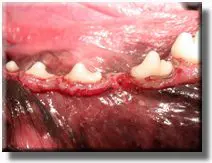

Patient with severely overgrown gums.

After gum reduction.